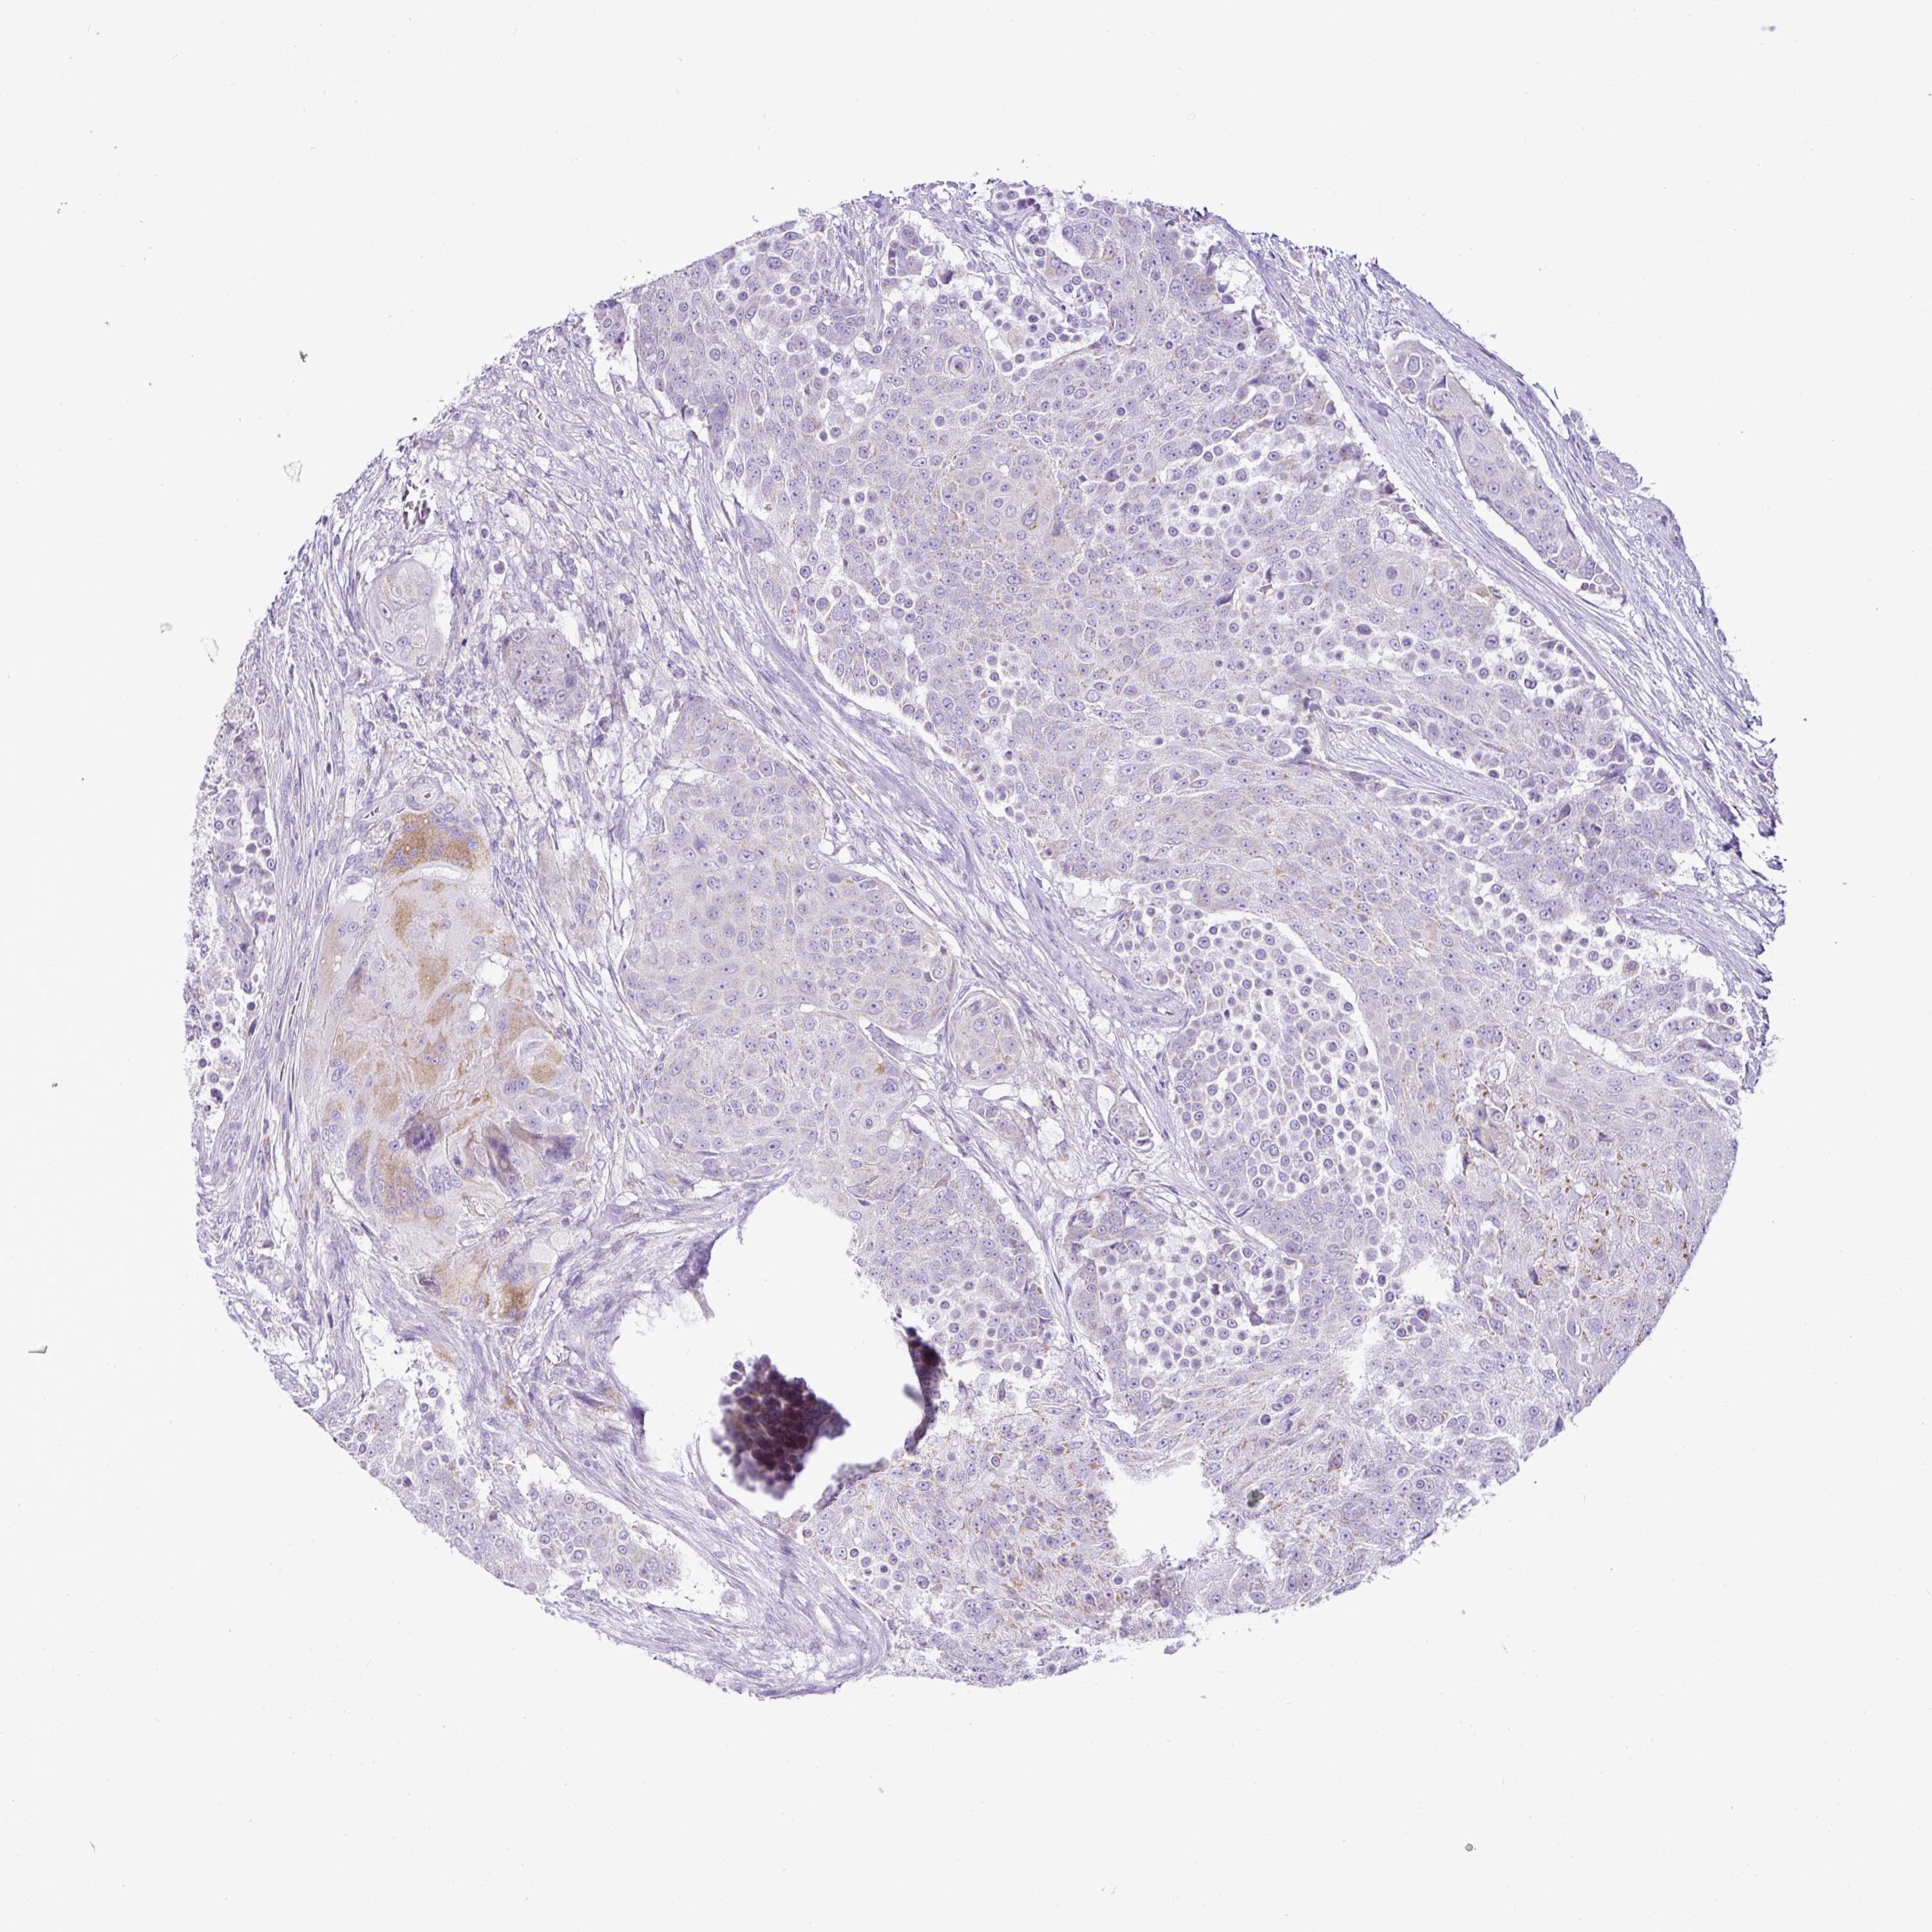

UROTHELIAL CANCER - Protein expressioni

A mouse-over function shows sample information and annotation data. Click on an image to view it in a full screen mode. Samples can be filtered based on level of antibody staining by selecting one or several of the following categories: high, medium, low and not detected. The assay and annotation is described here.

Note that samples used for immunohistochemistry by the Human Protein Atlas do not correspond to samples in the TCGA dataset.

Antibody stainingi

Antibody staining in the annotated cell types in the current human tissue is reported as not detected, low, medium, or high, based on conventional immunohistochemistry profiling in selected tissues. This score is based on the combination of the staining intensity and fraction of stained cells.

Each image is clickable and will lead to virtual microscopy that enables deeper exploration of all samples and also displays staining intensity scores, fraction scores and subcellular localization as well as patient and tissue information for each sample.

Antibody HPA011318

Antibody HPA054041

Staining

High

Medium

Low

Not detected

Intensity

Strong

Moderate

Weak

Negative

Quantity

>75%

75%-25%

<25%

None

Location

Nuclear

Cytoplasmic/membranous

Cytoplasmic/membranous,nuclear

Urothelial carcinoma, High grade

Urothelial carcinoma, NOS

Urothelial carcinoma, Low grade